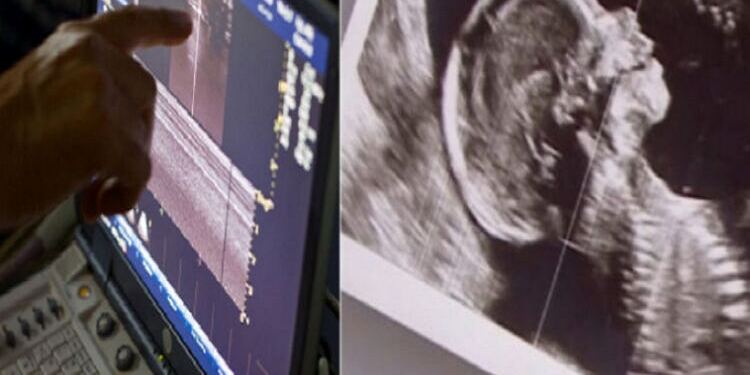

Η Nia ανακάλυψε, ότι ήταν έγκυος και πάλι. Όταν πήγε στο ιατρείο για υπερηχογράφημα, η νοσοκόμα ρώτησε αν η περίπτωση διδύμων είναι κοινή στην οικογένειά της. Τότε, κατάλαβε ότι είχε πάλι δίδυμα.

Αλλά όταν έφυγε από την αίθουσα των εξετάσεων για να χρησιμοποιήσει το μπάνιο, έμεινε συγκλονισμένη από αυτό που της είπε η νοσοκόμα όταν γύρισε: «Υπάρχουν τρία μωρά: Μωρό Α. Μωρό Β. Μωρό Γ.»

Το ζευγάρι άρχισε να μαντεύει τα φύλα των μωρών τους. Δεδομένου ότι είχαν ήδη τρεις γιους, ήθελαν να περίμεναν κορίτσια. Κατά τη διάρκεια ενός υπερηχογραφήματος, πήραν και πάλι την έκπληξη μιας ζωής.